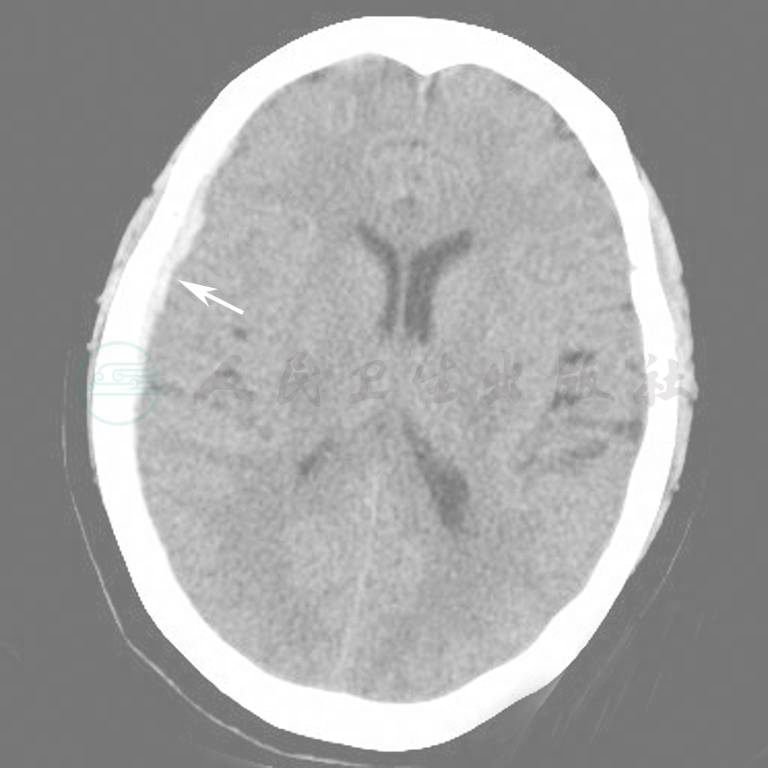

图6 双侧额叶出血

图7  右侧颞叶脑出血

图8  右侧基底节区脑出血

图9  脑干右份出血